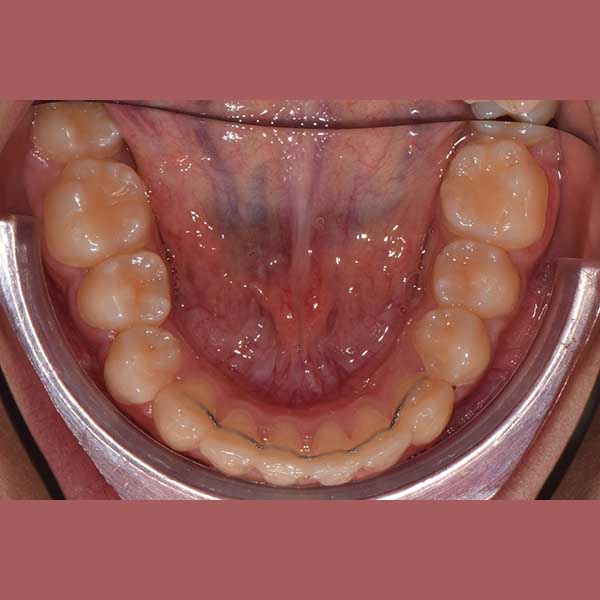

BEFORE

راجعتني هذه الشابة وهي تعاني من تراكب شديد في أسنانها العلوية والسفلية. المشكلة الأبرز كانت عدم وجود مسافة كافية لنابها العلوي الأيسر، مما أدى لبقائه مرتفعاً وبارزاً. كما كان الازدحام في الأسنان السفلية يسبب لها صعوبة في التنظيف وتراكماً سريعاً للجير.

كما تظهر الصور، تم حل مشكلة الازدحام بالكامل وتم رصف جميع الأسنان بشكل مثالي. استقر الناب العلوي في مكانه الطبيعي ضمن القوس السني، وأصبحت الأسنان السفلية متراصة وسهلة التنظيف. النتيجة هي ابتسامة جميلة وصحية منحت صديقتنا الشابة الثقة التي تستحقها.